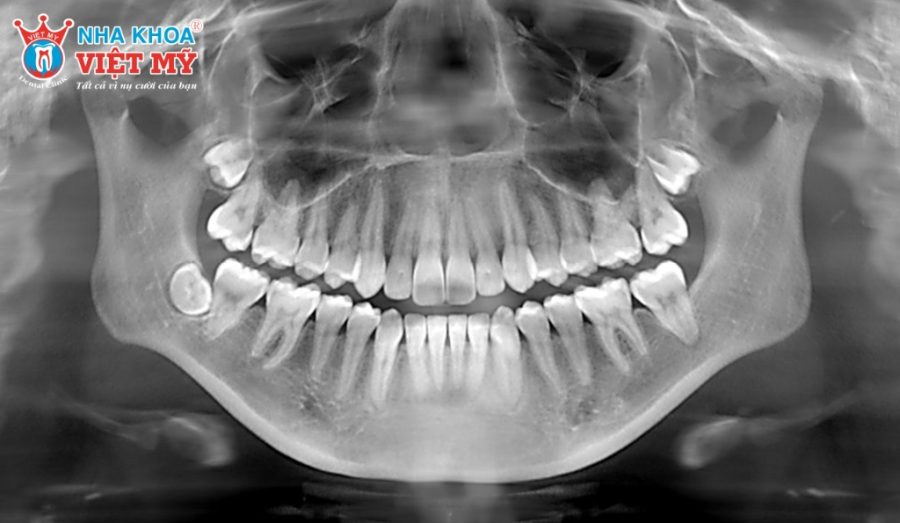

Chẩn đoán hình ảnh

Trong nhiều trường hợp, phim X-quang hoặc CT Cone Beam sẽ được chỉ định để kiểm tra xem có ổ viêm, áp xe hoặc tổn thương xương hàm quanh vùng nhổ răng hay không. Chẩn đoán hình ảnh giúp bác sĩ đánh giá mức độ lan rộng của nhiễm trùng.